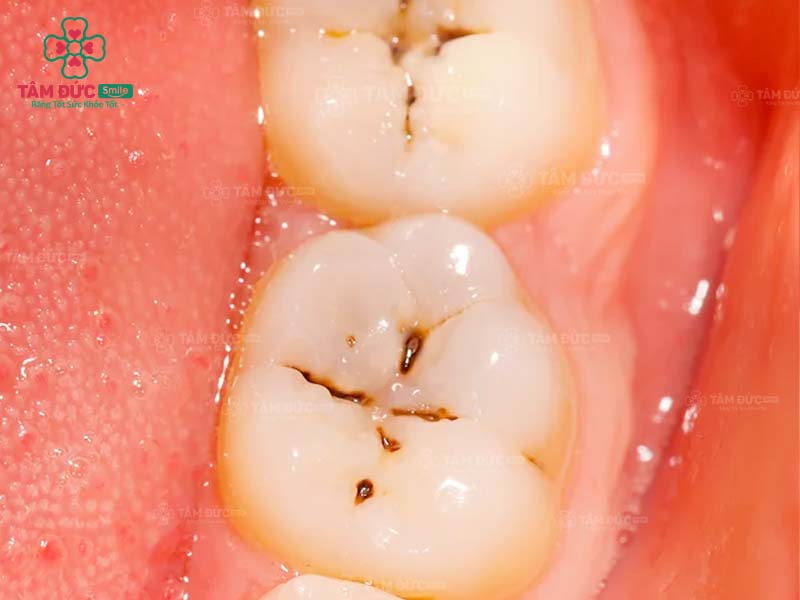

1.1. Răng bị sâu

Khi răng bị sâu, trên thân răng xuất hiện các lỗ nhỏ li ti. Đây chính là vị trí trú ngụ của hàng nghìn loại vi khuẩn. Cùng với thói quen chăm sóc răng miệng không tốt, ăn thực phẩm chứa nhiều đường, lỗ sâu răng sẽ lớn dần và gây đau nghiêm trọng. Nguy hiểm nhất chính là nhiễm trùng và mất răng vĩnh viễn.

Trám răng giúp lấp đầy các lỗ hổng trên thân răng. Nhờ đó, các triệu chứng khó chịu, biến chứng do răng sâu được loại bỏ triệt để. Thẩm mỹ của chiếc răng bị sâu nói riêng và cả hàm răng nói chung đều được phục hồi.